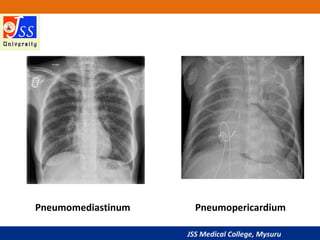

Pneumomediastinum Pneumopericardium

Mach Effect

• Sometimes a normal CXR will show

a thin, well-defined, black line

around one or both lateral margins

of the heart.

• An optical illusion resulting from

overlap of superimposed normal

structures.

• This illusion is known as a Mach

band or Mach effect